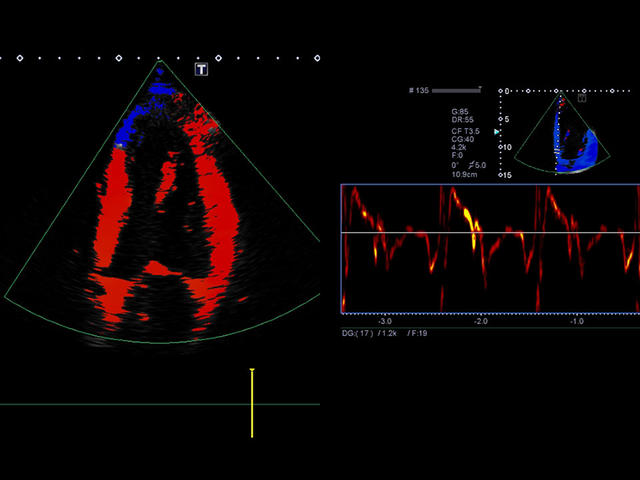

Xario 200 — это продуманная эргономика, впечатляющее качество изображения, отлаженный рабочий процесс и предельно высокая компактность. В Xario 200 цветовая доплеровская визуализация вышла на качественно новый уровень. Полностью интегрированная система управления данными пациентов и изображениями системы Xario обеспечивает удобный просмотр и простое управление исследованиями.

- Цветной, энергетический допплер - Colour Doppler Imaging/ Color Angio (CDI/CA).

- Тканевой допплер - Tissue Doppler Imaging (TDI).